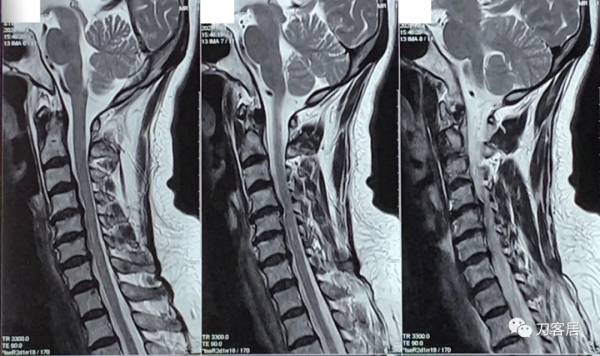

自帶腰椎MRI未見嚴重的椎間盤突出及椎管狹窄。自帶髖關節MRI未見異常,自帶胸椎MRI未見異常。自帶頸椎MRI提示頸4-5,頸5-6椎間盤突出,頸椎失穩。

圖1. 20210913腰椎MRI矢狀面T2相,未見明確的椎間盤突出及椎管狹窄。

圖2. 20210913腰椎MRI矢狀面T1相,未見明確的椎間盤突出及椎管狹窄。